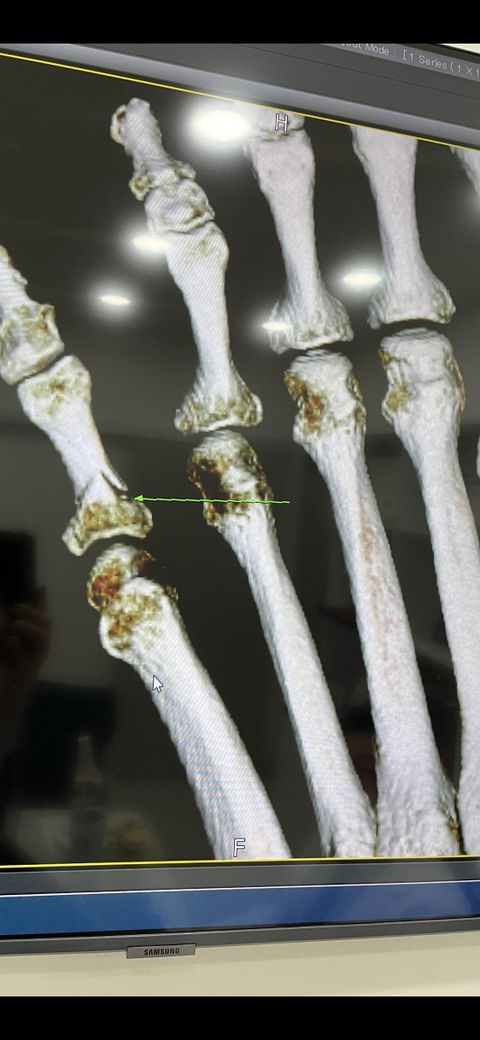

새끼 발가락 골절(ct사진 첨부) 수술이 꼭 필요한가요??

CT상으로는 뼈의 배열 자체가 틀어지지는 않았으므로 핀고정 없이 스플린트로 고정해볼 수 있을거라 예상되기는 합니다.

전위가 심해보이진 않으나 추시관찰 중에 전위가 진행되면 수술적 치료를 해야할수도 있습니다.

현재 전위가 많이 되어있지 않은 것처럼 보이나 다른 각도에서 확인도 필요하겠습니다. 일반적으로 반드시 수술해야 하는 골절은 환자에게 선택지를 주는 경우는 흔치 않으며 이는 수술로 인해 얻는 장단점이 명확치 않아 그럴 수도 있습니다.

현 상태로는 반드시 수술이 필요한 상태는 아닌 것으로 보입니다.